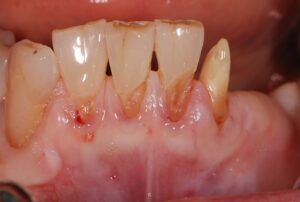

歯周病治療

歯周外科治療

Case Studies